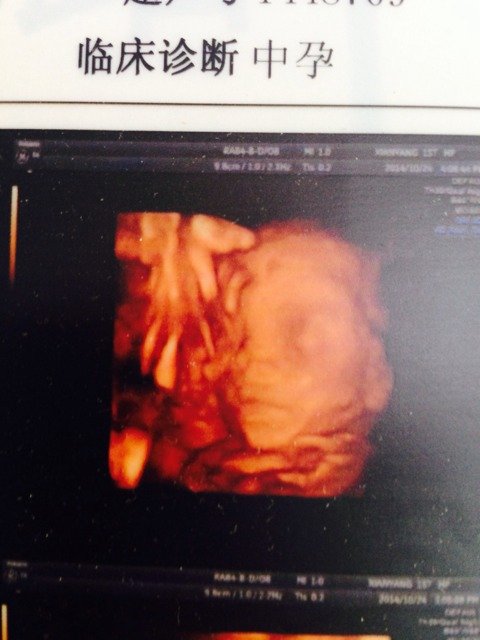

看一下男娃还是女娃 看一下男娃还是女娃 点击展开 红塬坊血麦锅巴 2014-11-22 19:45 为您推荐: 其他回答 您这图片是宝宝的面部,没办法分辨男女的, 可爱优优6688 2014-11-22 23:00 这样看不出来的! 演じ 2014-11-22 20:00 好像是男孩 天下父母心 2014-11-22 19:52 这是看不出的! 丞曦 2014-11-22 19:49 像男孩的脸 桔梗花のˇ 2014-11-22 19:48 加载更多 相关问题 帮忙看一下,我不太会看 看的出来男娃还是女娃吗 宝妈们围观过来,怀孕期间您们都梦见啥拉???最终都生了女娃还是男娃啦???